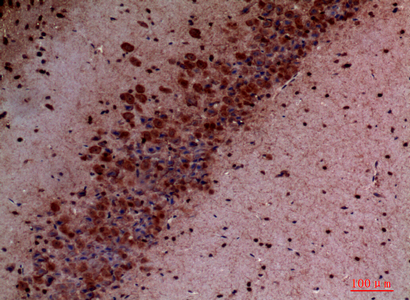

IHC 1/50-1/100 Human,Mouse,Rat

The PI3 kinase p110 delta (PI3Kδ) antibody is a research tool designed to detect and study the p110δ catalytic subunit of phosphoinositide 3-kinase (PI3K), a lipid kinase critical for intracellular signaling. PI3Kδ belongs to the class IA PI3K family, which consists of a regulatory subunit (p85) and a catalytic subunit (p110). Among the four p110 isoforms (α, β, γ, δ), p110δ is primarily expressed in leukocytes and plays a key role in immune cell activation, proliferation, and survival. It is encoded by the PIK3CD gene and is activated by receptor tyrosine kinases or G-protein-coupled receptors.

PI3Kδ dysfunction is implicated in immune disorders, inflammatory diseases, and cancers, particularly B-cell malignancies like chronic lymphocytic leukemia. Antibodies targeting p110δ enable researchers to investigate its expression, localization, and activity in normal and pathological contexts. These antibodies are widely used in techniques such as Western blotting, immunohistochemistry, and flow cytometry to assess protein levels or phosphorylation status, aiding in mechanistic studies of PI3Kδ signaling pathways.